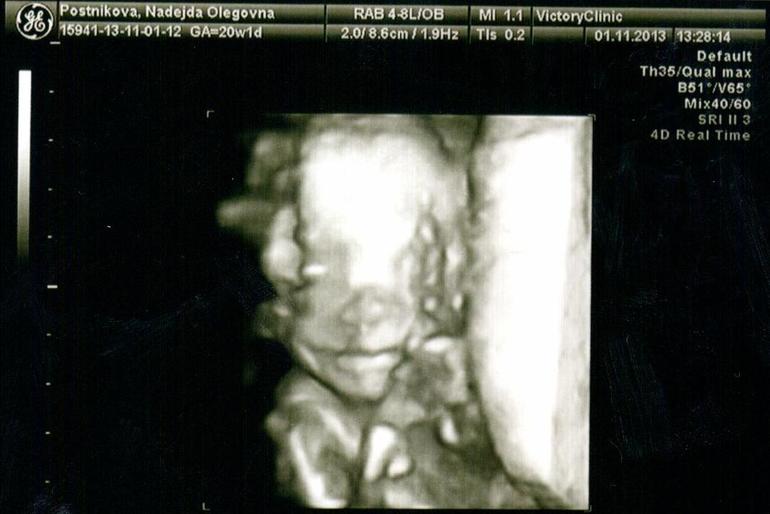

Сегодня я по особенному счастливая и наш с пузиком экватор - не единственная тому причина, причин у нас много - сегодня мы были на УЗИ (подглядывали за нашим сокровищем), до сих пор эмоции переполняют… :) У нас все хорошо, развиваемся по сроку, уже довольно-таки большие - 330 грамм )) Мы узнали пол, я аж прослезилась от счастья ))) Муж тоже очень рад, от чего я счастливее вдвойне )))

Собственно говоря, вот и мы:

На УЗИ мы спали, так что выкрутасов типа сальто мы не увидели (как на 12 неделях), но УЗИстка сказала запасаться книгами по воспитанию, т.к. ребеночек уже очень характерный )) А еще очень скромный, малыш закрывал себе постоянно личико, при чем не всегда ручками, бывало и ножками )) От этого мне пришлось постоянно вертеться с бока на бок и кашлять, чтобы хоть как то заставить его показаться нам, в конце даже удалось разбудить. Нам сделали аж 12 фото и 24 видеоролика )))

Нам сказали, что головка у нас долихоцефалической формы (такая обычно у детишек после естественных родов, т.е. чуть вытянутая, но сказали, что до родов она еще изменится) и еще утолщенная плацента, вот это меня не очень порадовало :( На ЗППП сдавала, все чисто, анемия у меня совсем слабая, все другие причины тоже ко мне не относятся, так что повлиять могла на это либо простуда, перенесенная в первом триместре, либо мой офисный режим работы (отсутствие кислорода), теперь просто уверена как никогда, что морской воздух мне пойдет на пользу )))